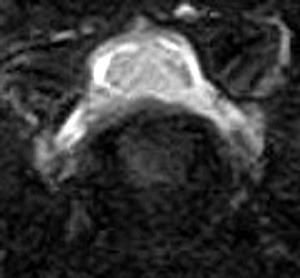

5~6歳以上の去勢手術をしていないオス犬に多い病気ですが、メス犬や去勢した犬に起こることもあります。お尻の筋肉が萎縮した結果、筋肉の隙間から直腸や膀胱が皮膚の下にとびでてしまいます。これにより便が出にくくなったり膀胱炎になったりします。手術をすることで機能回復および今後の致死的な状況を回避することができます。当院では去勢手術→結腸固定→前立腺固定→骨盤隔膜構成筋の縫縮→内閉鎖筋フラップ→浅臀筋フラップの順で通常腹側・臀部左右両側同時に行います。また老化以外に、筋肉が萎縮する原因があったり、腹圧がかかる原因があったりする場合も多いので、再発防止のためそれらの診断・治療も重要です。今回のワンちゃんも無事手術も終わり元気に退院しました。よかったね。